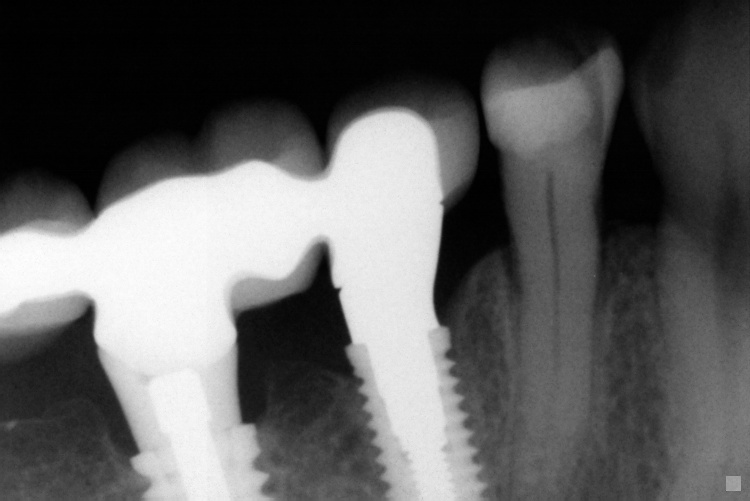

Name Last modified Size Description Parent Directory - IO000001.jpg 2020-07-28 13:36 71K IO000002.jpg 2020-07-28 13:36 88K IO000003.jpg 2020-07-28 13:36 82K IO000004.jpg 2020-07-28 13:36 85K